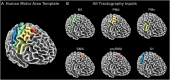

The purpose of this study was to develop a high-resolution sensorimotor area tract template (SMATT) which segments corticofugal tracts based on 6 cortical regions in primary motor cortex, dorsal premotor cortex, ventral premotor cortex, supplementary motor area (SMA), pre-supplementary motor area (preSMA), and primary somatosensory cortex using diffusion tensor imaging. Individual probabilistic tractography analyses were conducted in 100 subjects using the highest resolution data currently available. Tractography results were refined using a novel algorithm to objectively determine slice level thresholds that best minimized overlap between tracts while preserving tract volume. Consistent with tracing studies in monkey and rodent, our observations show that cortical topography is generally preserved through the internal capsule, with the preSMA tract remaining most anterior and the primary somatosensory tract remaining most posterior. We combine our results into a freely available white matter template named the SMATT. We also provide a probabilistic SMATT that quantifies the extent of overlap between tracts. Finally, we assess how the SMATT operates at the individual subject level in another independent data set, and in an individual after stroke. The SMATT and probabilistic SMATT provide new tools that segment and label sensorimotor tracts at a spatial resolution not previously available.